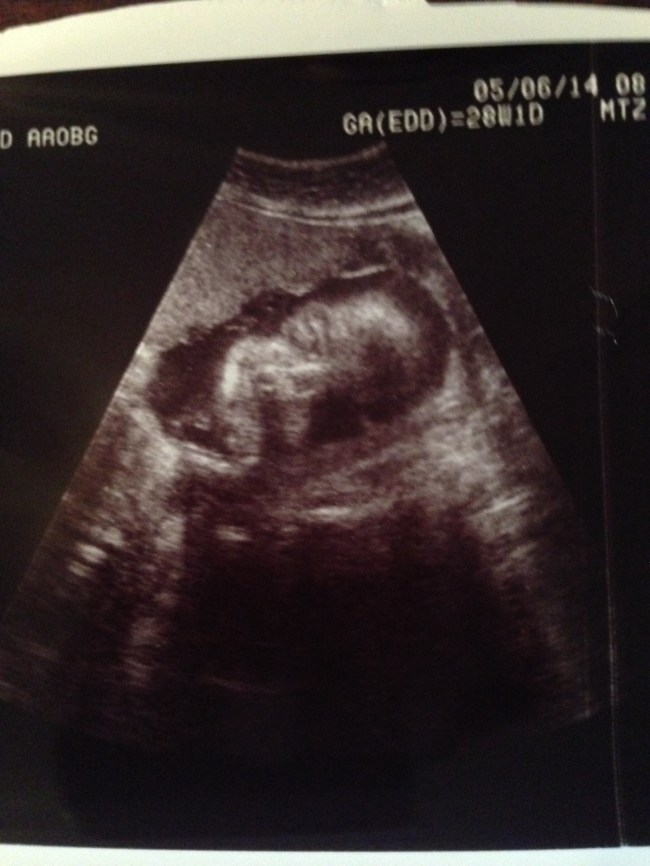

I also had a doctor appointment Monday morning and Scarlett looks perfect.

Baby Scarlett skeleton face! Eek! It’s a perfect skeleton face, though!